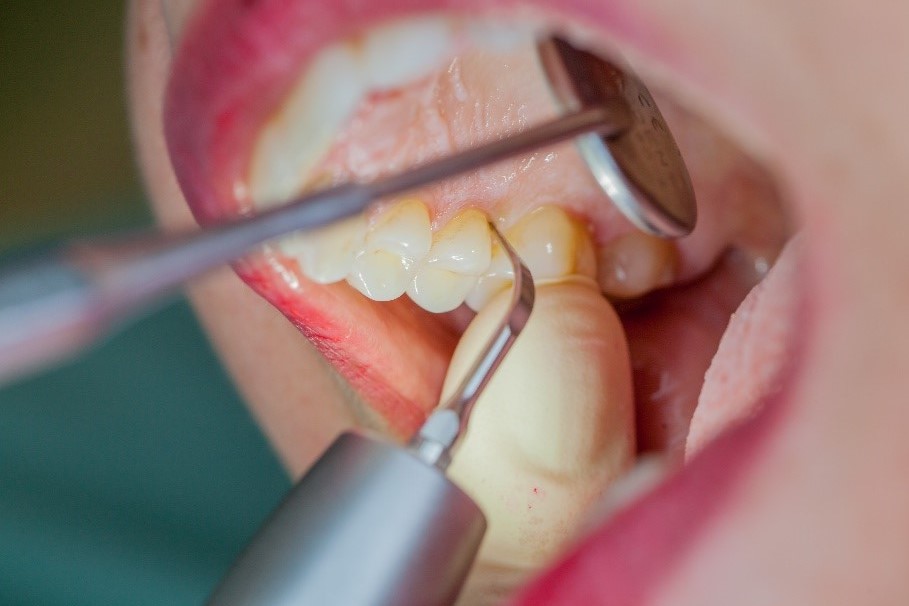

Dans les soins de suivi parodontal post-implantation, les concrétions molles (biofilm) et dures doivent être éliminées régulièrement par des techniques de nettoyage mécanique professionnelles. [16, 17] Dans les zones subgingivales et supragingivales, on utilise généralement pour cela des dispositifs à ultrasons (Fig. 4) en combinaison avec des instruments manuels si nécessaire.